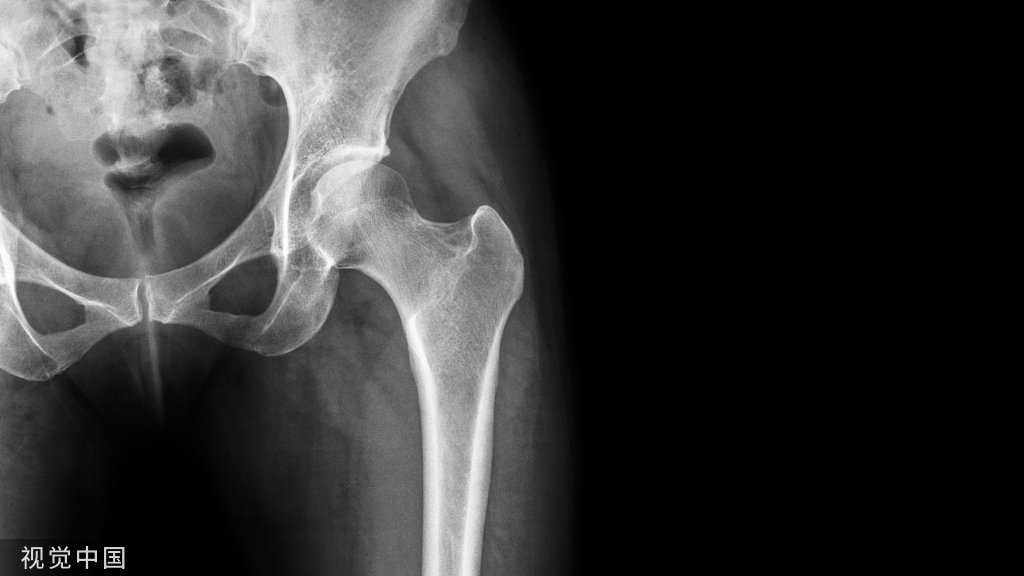

手术患者术前和术后的x线图像。(a)掌骨级联线AP x线。这些线沿着掌骨的轴线画;绿色表示解剖性,红色表示脱位,因为它不与其他关节相交。(b)术前斜位x线片。